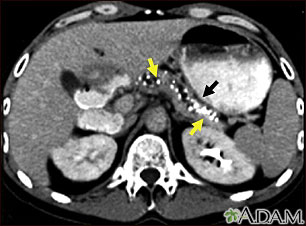

Tomografía computarizada de una pancreatitis crónica

TC del abdomen superior que muestra múltiples calcificaciones blancas. Éstas se presentan en la pancreatitits crónica.